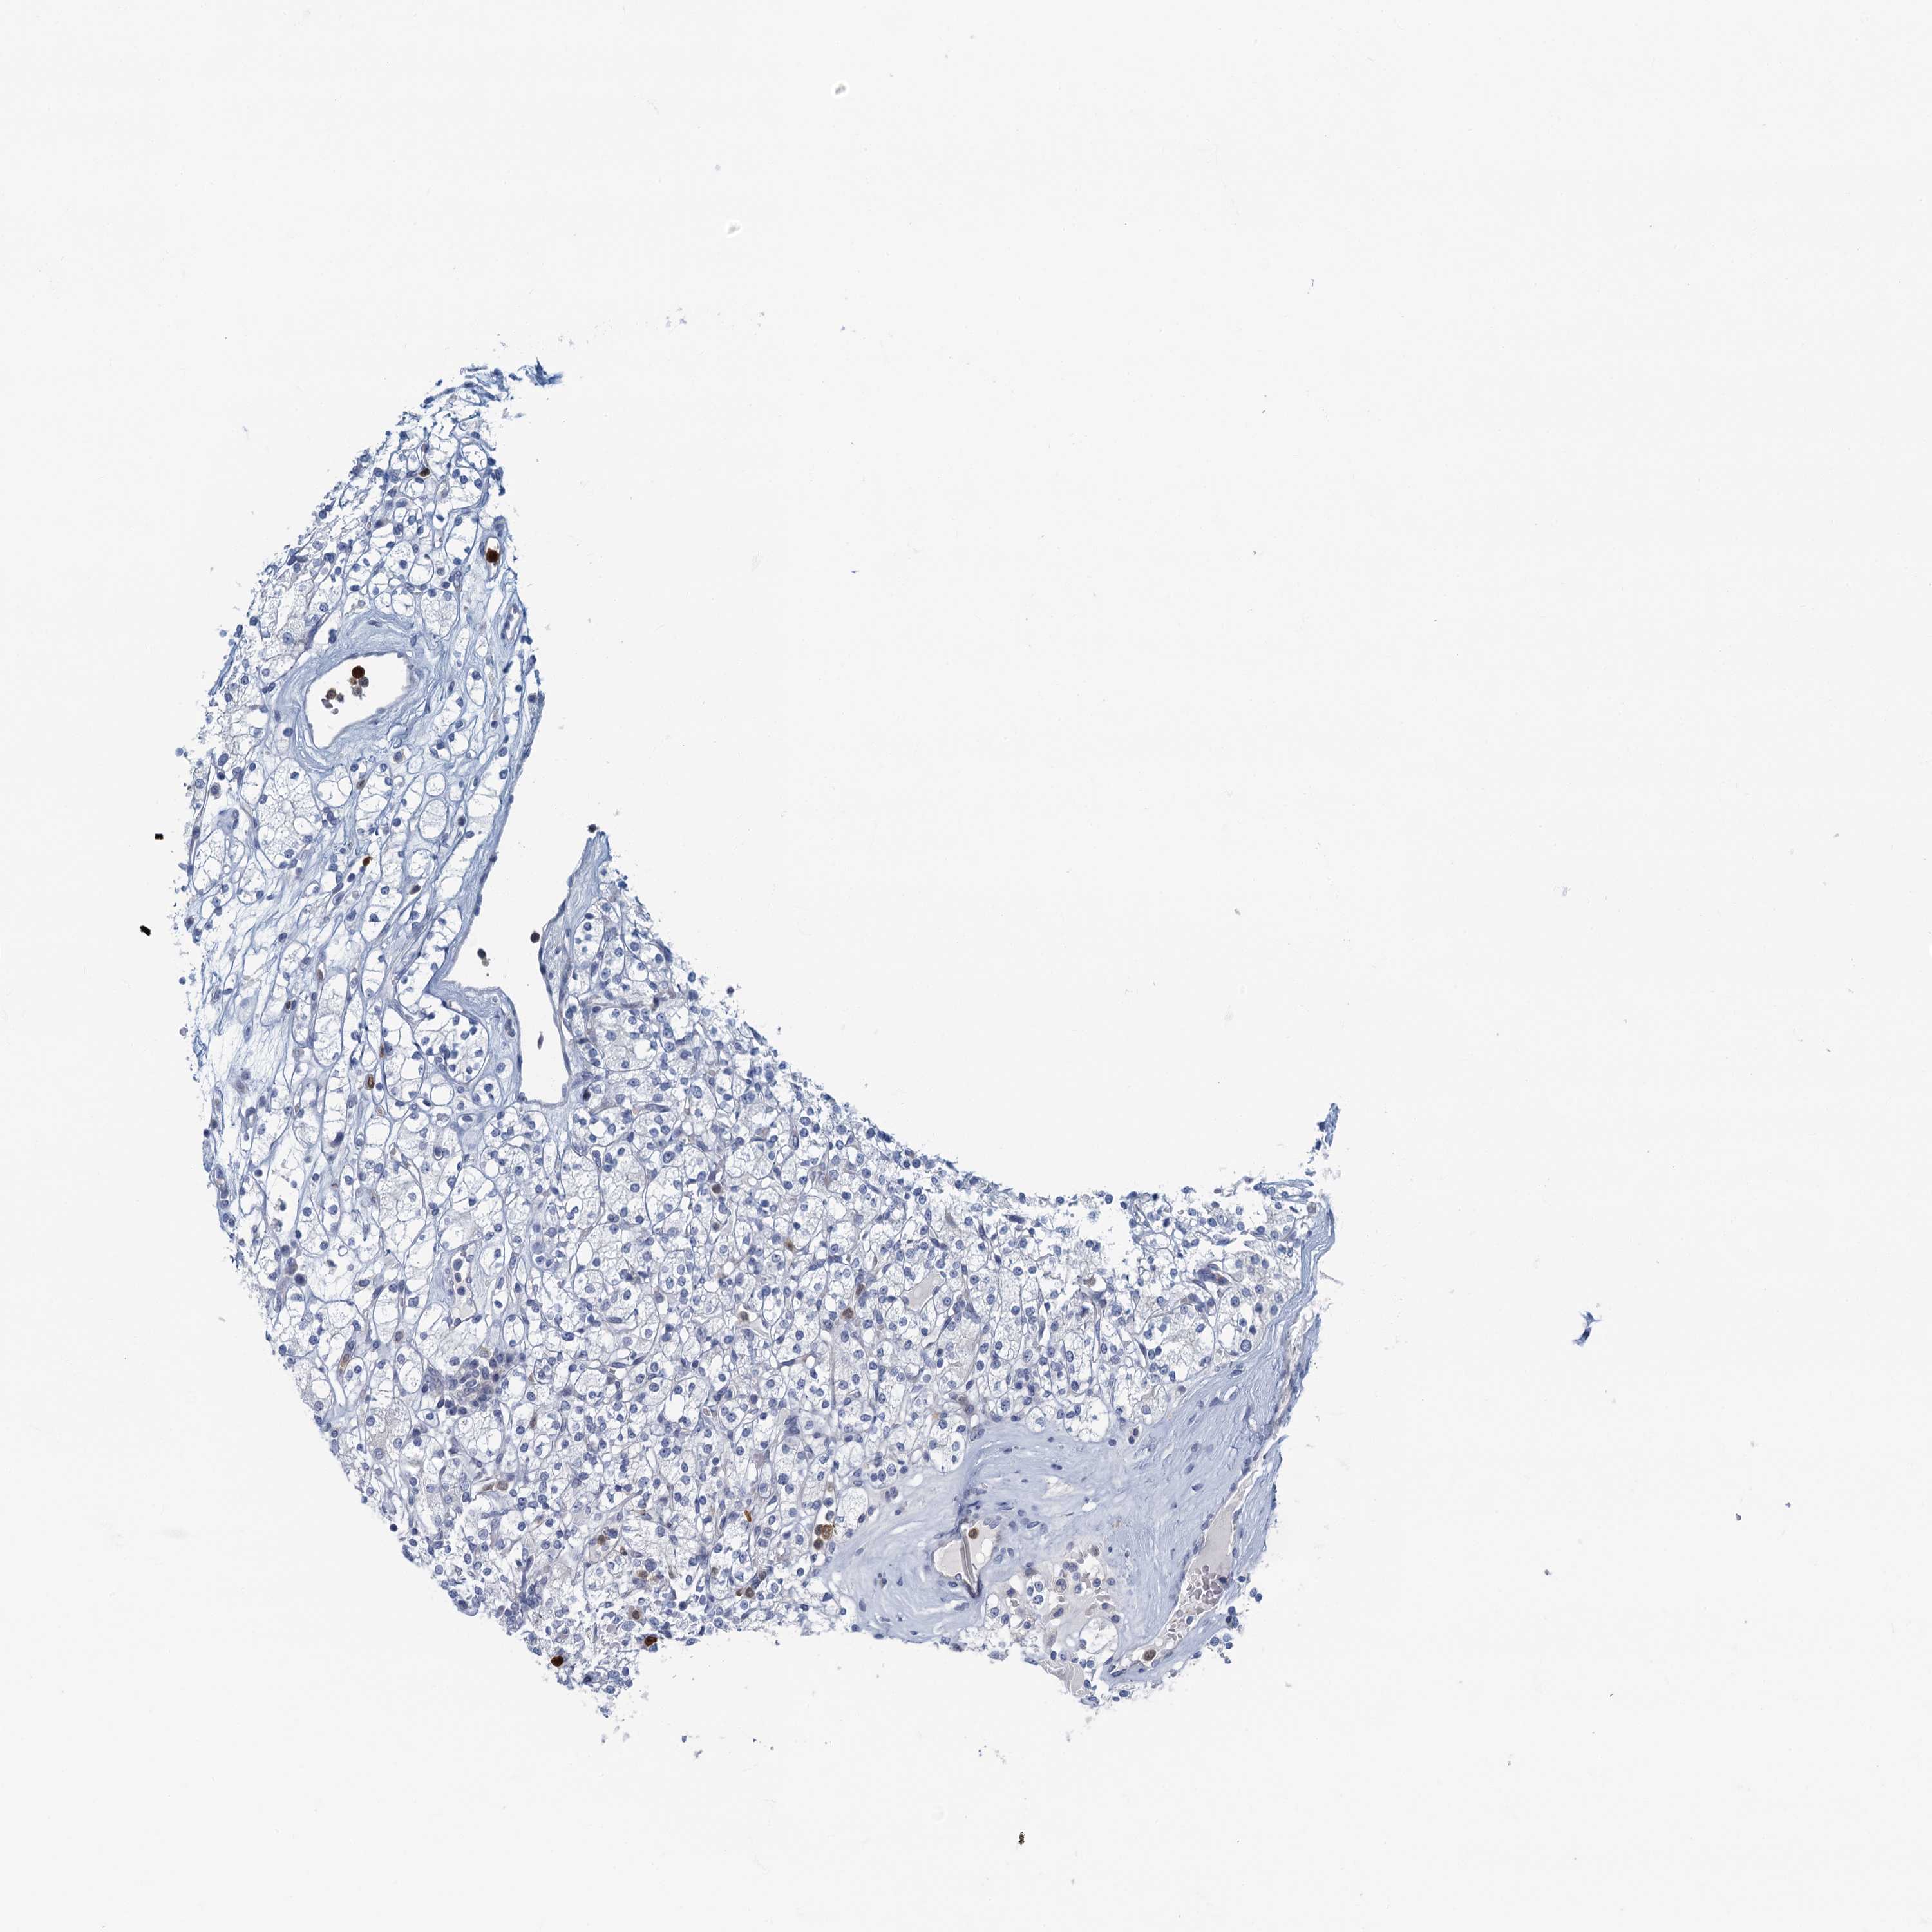

KIDNEY RENAL PAPILLARY CELL CARCINOMA (TCGA) - Interactive survival scatter ploti

The Survival Scatter plot shows the clinical status (i.e. dead or alive) for all individuals in the patient cohort, based on the same data that underlies the corresponding Kaplan-Meier plots. Patients that are alive at last time for follow-up are shown in blue and patients who have died during the study are shown in red.

The x-axis shows the expression levels (FPKM) of the investigated gene in the tumor tissue at the time of diagnosis. The y-axis shows the follow-up time after diagnosis (years). Both axes are complimented with kernel density curves demonstrating the data density over the axes. The top density plot shows the expression levels (FPKM) distribution among dead (red) and alive patients (blue). The right density plot shows the data density of the survived years of dead patients with high and low expression levels respectively, stratified using the cutoff indicated by the vertical dashed line through the Survival Scatter plot. This cutoff is automatically defined based on the FPKM cutoff that minimizes the p-score. The cutoff can be changed by dragging the vertical line or by entering a cutoff value in the square labeled "Current cut-off".

Under the Survival Scatter plot the p-score landscape (black curve; left axis) is shown together with dead median separation (red curve; right axis). Dead median separation is the difference in median mRNA expression between patients who have died with high and low expression, respectively. It is calculated as follows: median FPKM expression of dead patients with high expression - median FPKM expression of dead patients with low expression. This is intended to aid the user in visually exploring custom cutoffs and the associated p-scores and dead median separation.

Individual patient data is displayed and can be filtered by clicking on one or more of the category buttons on the top of the page. Categories describing expression level and patient information include: high, low, alive, dead, female, male and tumor stages. The scale of the x-axis can be toggled between linear and log-scale by clicking on the "x log" button. Mouse-over function shows TCGA ID, patient information and mRNA expression (FPKM) for each patient.

& Survival analysisi

Kaplan-Meier plots summarize results from analysis of correlation between mRNA expression level and patient survival. Patients were divided based on level of expression into one of the two groups "low" (under cut off) or "high" (over cut off). X-axis shows time for survival (years) and y-axis shows the probability of survival, where 1.0 corresponds to 100 percent.

ANKDD1A is not prognostic in Kidney Renal Papillary Cell Carcinoma (TCGA)

Best expression cut offi

Based on the FPKM value of each gene, patients were classified into two groups and association between prognosis (survival) and gene expression (FPKM) was examined. The best expression cut-off refers the FPKM value that yields maximal difference with regard to survival between the two groups at the lowest log-rank P-value. Best expression cut-off was selected based on survival analysis .

When clicking on this number, the vertical dashed line indicating cut-off, the interactive survival plot, and the Kaplan-Meier curve will be adjusted to show results based on the best expression cut-off.

: 3.84